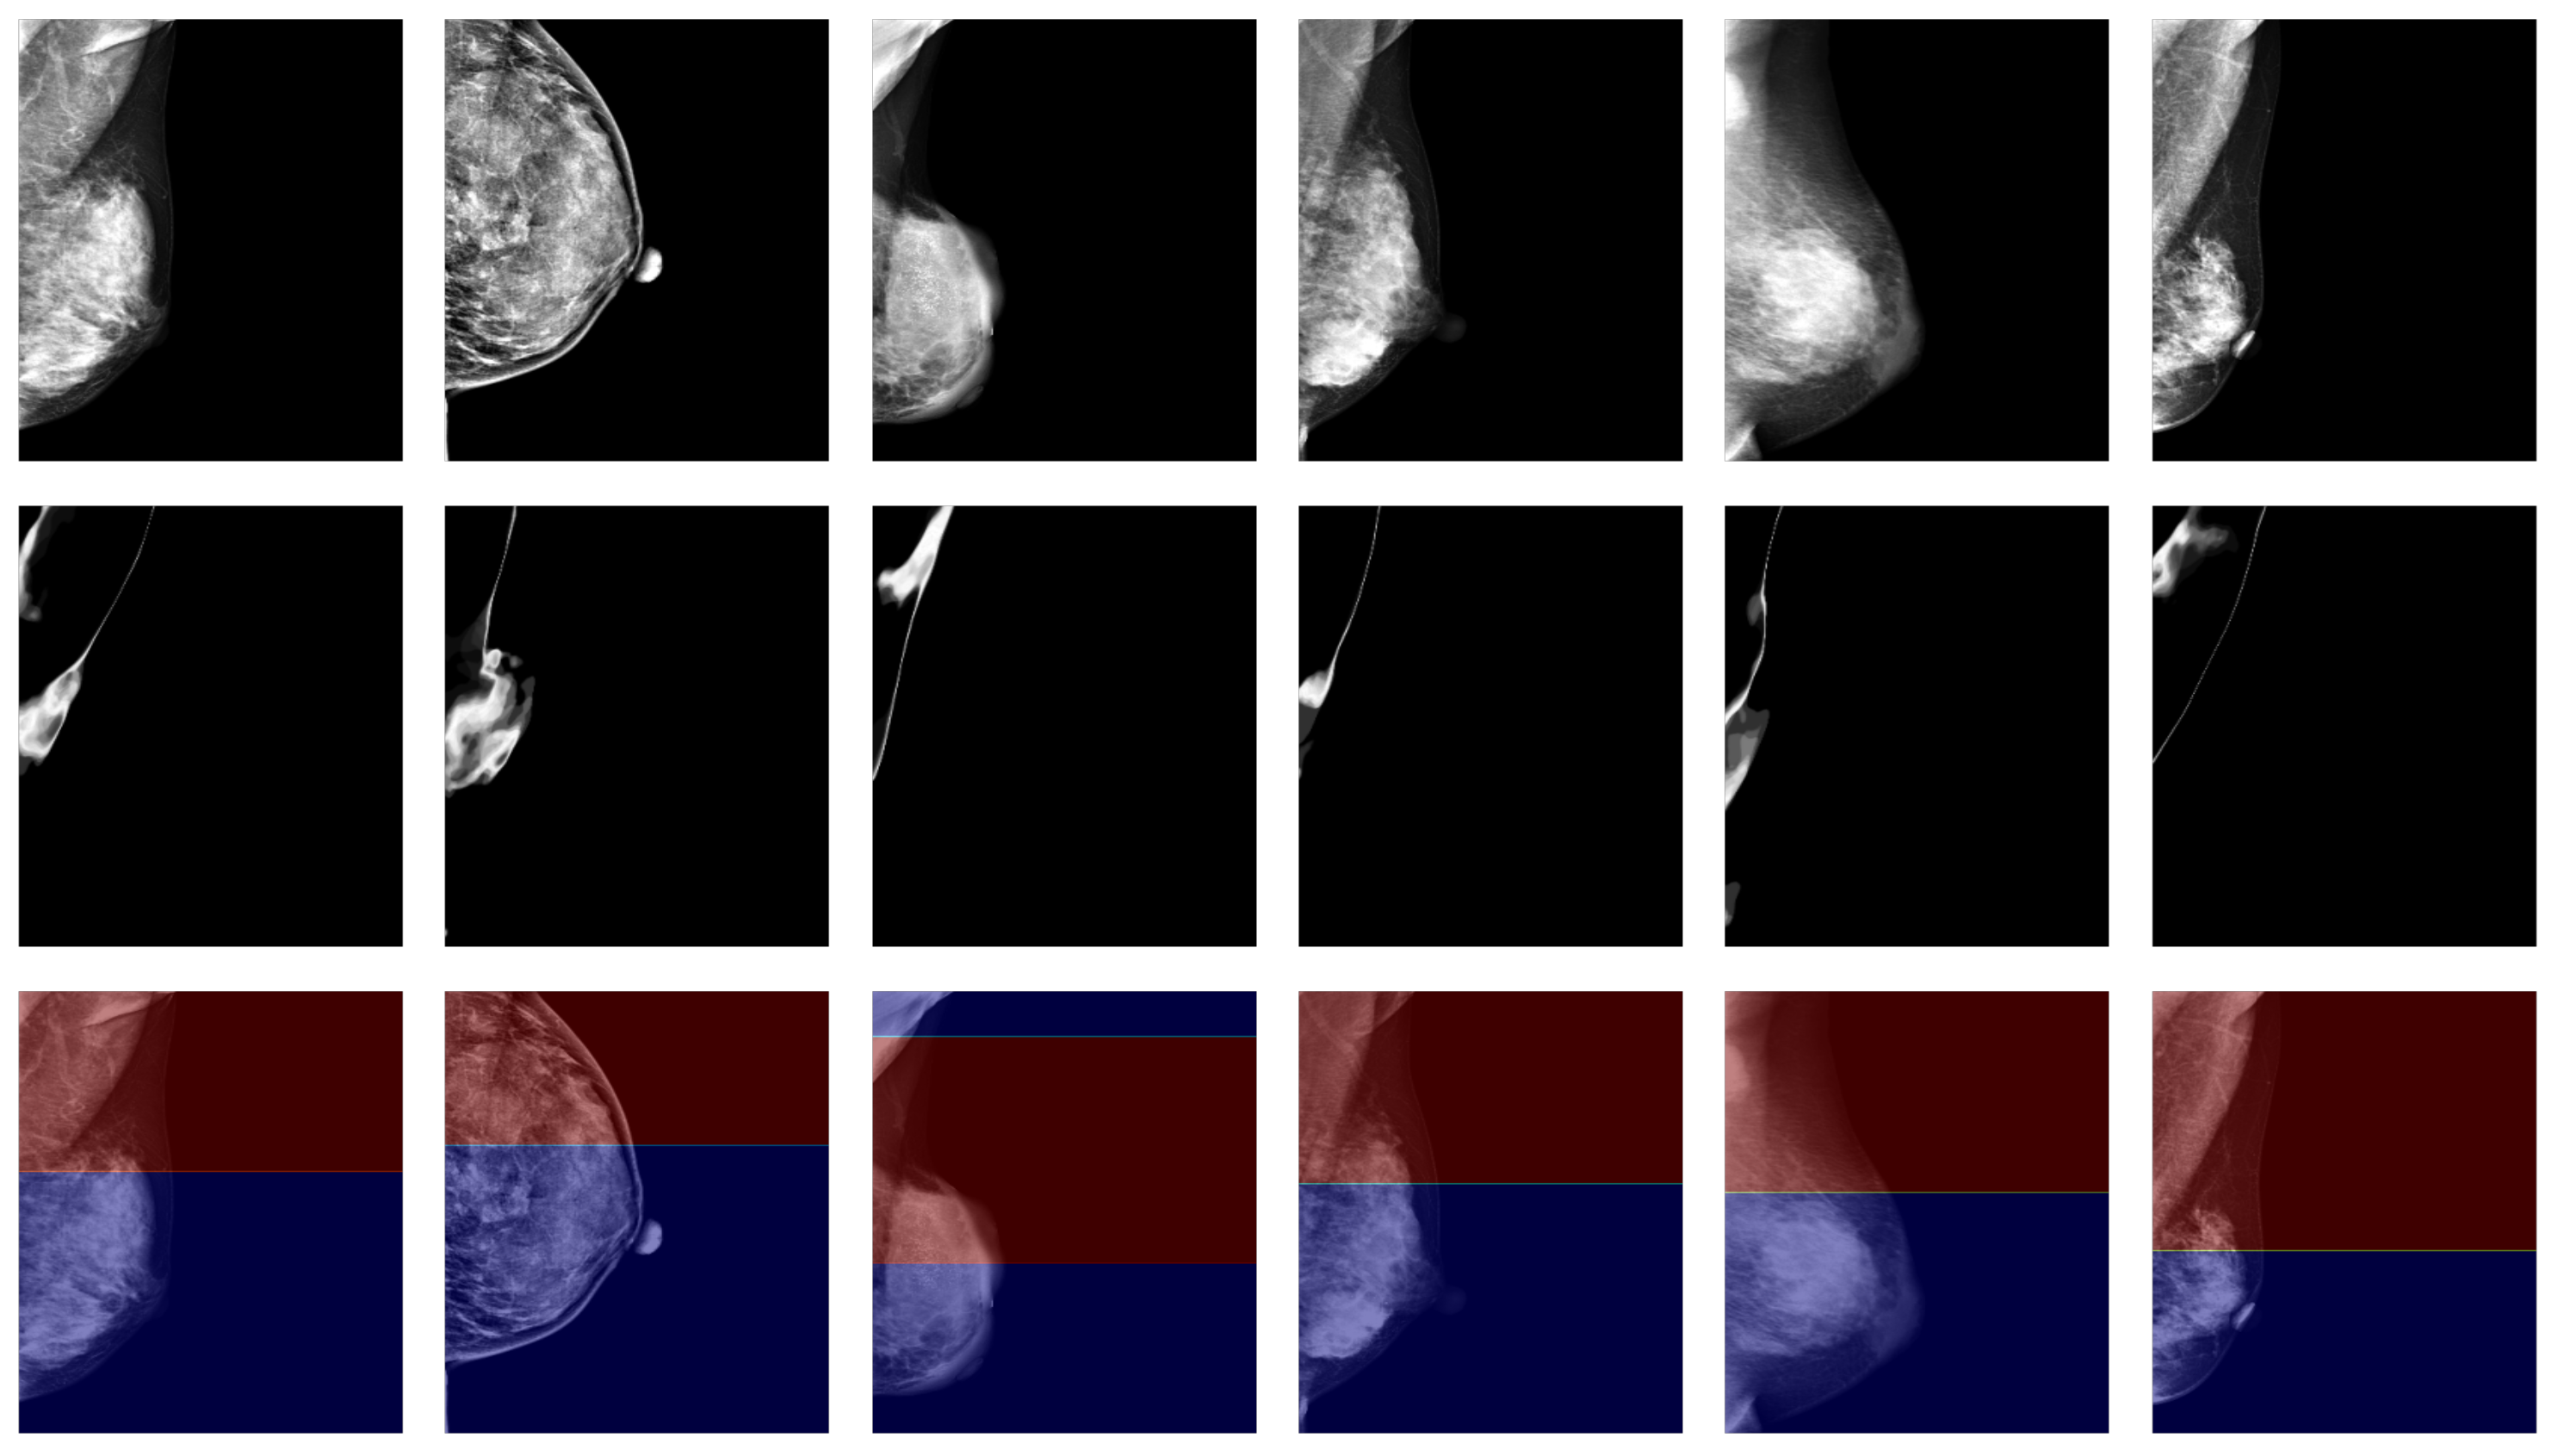

3.2. Qualitative Evaluation